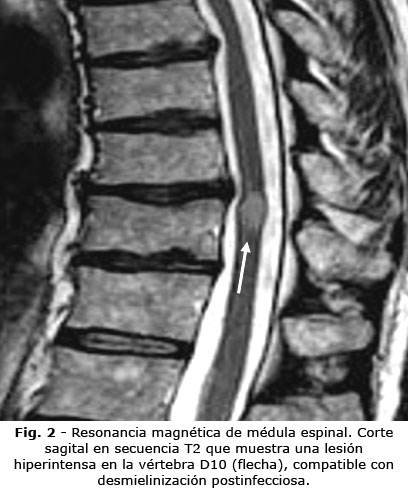

La resonancia magnética mostró lesiones hiperintensas en T2/FLAIR (Fig. 1) y en mesencéfalo y médula dorsal (D10) (Fig. 2), compatibles con desmielinización.

El cuadro clínico observado, se caracteriza por la tríada de afectación cerebelosa, piramidal y neuropsiquiátrica; reproduce el patrón descrito en el 78 % de los casos analizados por Zuhorn F y otros.(9) Desde la perspectiva imagenológica, las lesiones desmielinizantes en el mesencéfalo y la médula dorsal concuerdan con la localización típica reportada, en la cual, el 65 % de los casos muestra afectación predominante del tronco cerebral y la médula espinal.(10) Este patrón topográfico resulta clave para el diagnóstico diferencial con otras entidades, como la esclerosis múltiple y la neuromielitis óptica, que fueron descartadas en el paciente mediante criterios clínicos e imagenológicos establecidos.(11)

Las implicaciones clínicas de este caso son multifacéticas. Primero, refuerza la necesidad de la vigilancia neurológica prolongada, después de la COVID-19, independientemente de la gravedad inicial de la infección. Segundo, destaca el valor de la resonancia magnética como herramienta diagnóstica esencial en entornos con recursos limitados. Tercero, subraya la importancia de iniciar la terapia inmunomoduladora empírica, cuando la sospecha clínica sea elevada, particularmente si no se disponen de pruebas avanzadas para confirmar el diagnóstico.(18,19)